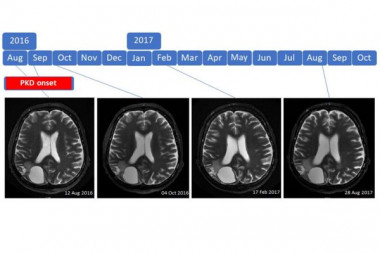

Introduction: Prognosis for patients with high-grade brain tumor is poor and survival did neither substantially change with advances in chemotherapy, radiotherapy and molecular profiling. Ketogenic diets have been suggested as a promising alternative therapy.